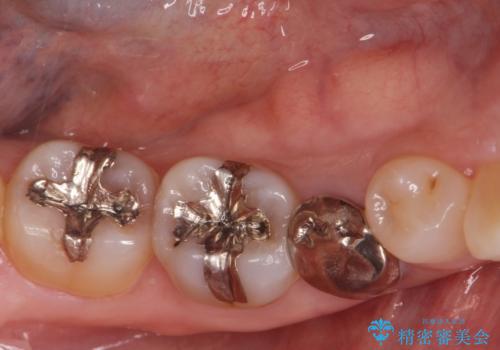

- 30代男性

- 歯ぎしりが気になるとの事で来院。

しっかりしたナイトガードが欲しいとの事だったので自費のナイトガードのご案内をしました。

ナイトガードは夜寝ている時、無意識に歯ぎしりをして歯がすり減ることを防ぐことがあります。また、歯が割れたり欠けたりするのも防いでくれます。